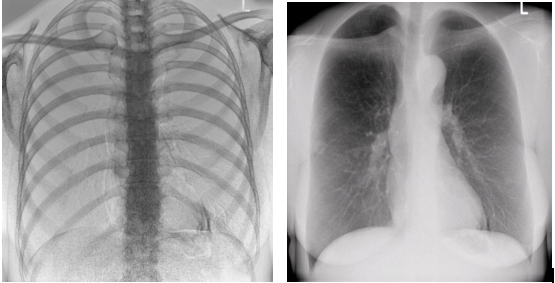

2)图像质量无畸变,无失真

高效动态平板技术,图像不会有几何畸变,提供高分辨率和精确的图像,为临床诊断提供精准依据。

最高帧速可达30帧/秒,获得与静态采集相媲美的高清流畅影像;

采用先进的脉冲透视技术,呈现更优图像空间分辨率、低对比度分辨率、灰阶范围,为精准诊断提供可靠依据。

4)透视+高清点片

在可视过程或回放过程中,如发现疑似病灶,可进行毫秒级高清点片,随时抓取单帧图像,精准捕抓病灶,便于医生进一步诊断分析,减少误诊,并有助于快速编制报告。